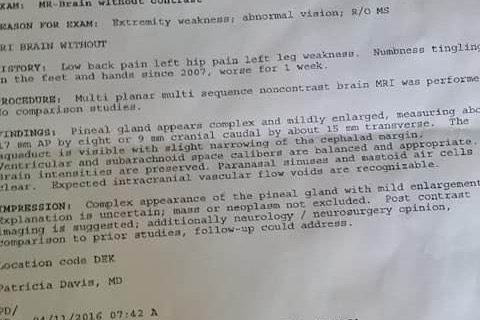

The medical journeyI have been diagnosed with a symptomatic growth located in my pineal gland. I experienced my first symptom in 2006 and have seen so many doctors that have tried different treatments and have been given different diagnosis. There was no definitive explanation as to why these issues have come about but I have been labeled with peripheral neuropathy, CRPS, migraines, anisocoria, essential tremors, light and sound sensitivity, unexplained nausea, and tinnitus over the past 12 years. There were no abnormalities or explanations on tests with the exception of an enlarged and complex pineal gland.

In 2016, I found a facebook group called Pineal Cysts and Tumors that has not only supported me emotionally, but also provided me with valuable information that linked me with doctors educated in my specific illness. Other members in this group had similar symptoms as mine and I was amazed that most doctors had very little knowledge of the pineal gland. In September, I became ill with hives and received what should have been a simple and easy treatment. I then became violently ill and felt myself take a turn for the worse. I have not been able to work or petsit since the beginning of September. Standing is unbearable after 15 minutes. Sensitivity to light and noise noticed. When people speak in a regular voice I think they are shouting. I can’t stand fluorescent lights. Stress seems to aggravate everything at this point. I noticed recently I get angry easily and am more impatient from when I last thought I was becoming impatient. I am easily lost in the middle of a sentence and I will pause until I can regain my train of thought. (Thanks everyone for finishing my sentences and reminding me what we were talking about!) I get nausea randomly, or if their is an unexpected texture when eating. Debilitating migraines! Recently, I experienced my first aural migraine. My social, home and work life have suffered dramatically over the past 6 months. Lately I feel so tired; sleeping in a dark quiet room has become my life. I feel my quality of life has declined for so many years, but this year has been nearly unbearable. I don’t think there any other options at this point.  After feeling as if I did my "due diligence", I reached out to Dr. Sunil J. Patel in Charleston, SC after reading that he is one of the 5 doctors in the WORLD that regularly deal with the pineal gland. I sent my MRIs, CT scans, medical records and a list/timeline of my symptoms to Dr. Patel and was told " I can cure you" on November 16th 2018. My surgery is scheduled December 19th, 2018 in Charleston SC. https://www.broadcastmed.com/neurology/7419/videos/resection-of-pineocytomas-offers-symptom-relief

After feeling as if I did my "due diligence", I reached out to Dr. Sunil J. Patel in Charleston, SC after reading that he is one of the 5 doctors in the WORLD that regularly deal with the pineal gland. I sent my MRIs, CT scans, medical records and a list/timeline of my symptoms to Dr. Patel and was told " I can cure you" on November 16th 2018. My surgery is scheduled December 19th, 2018 in Charleston SC. https://www.broadcastmed.com/neurology/7419/videos/resection-of-pineocytomas-offers-symptom-relief  Moving forward and costs